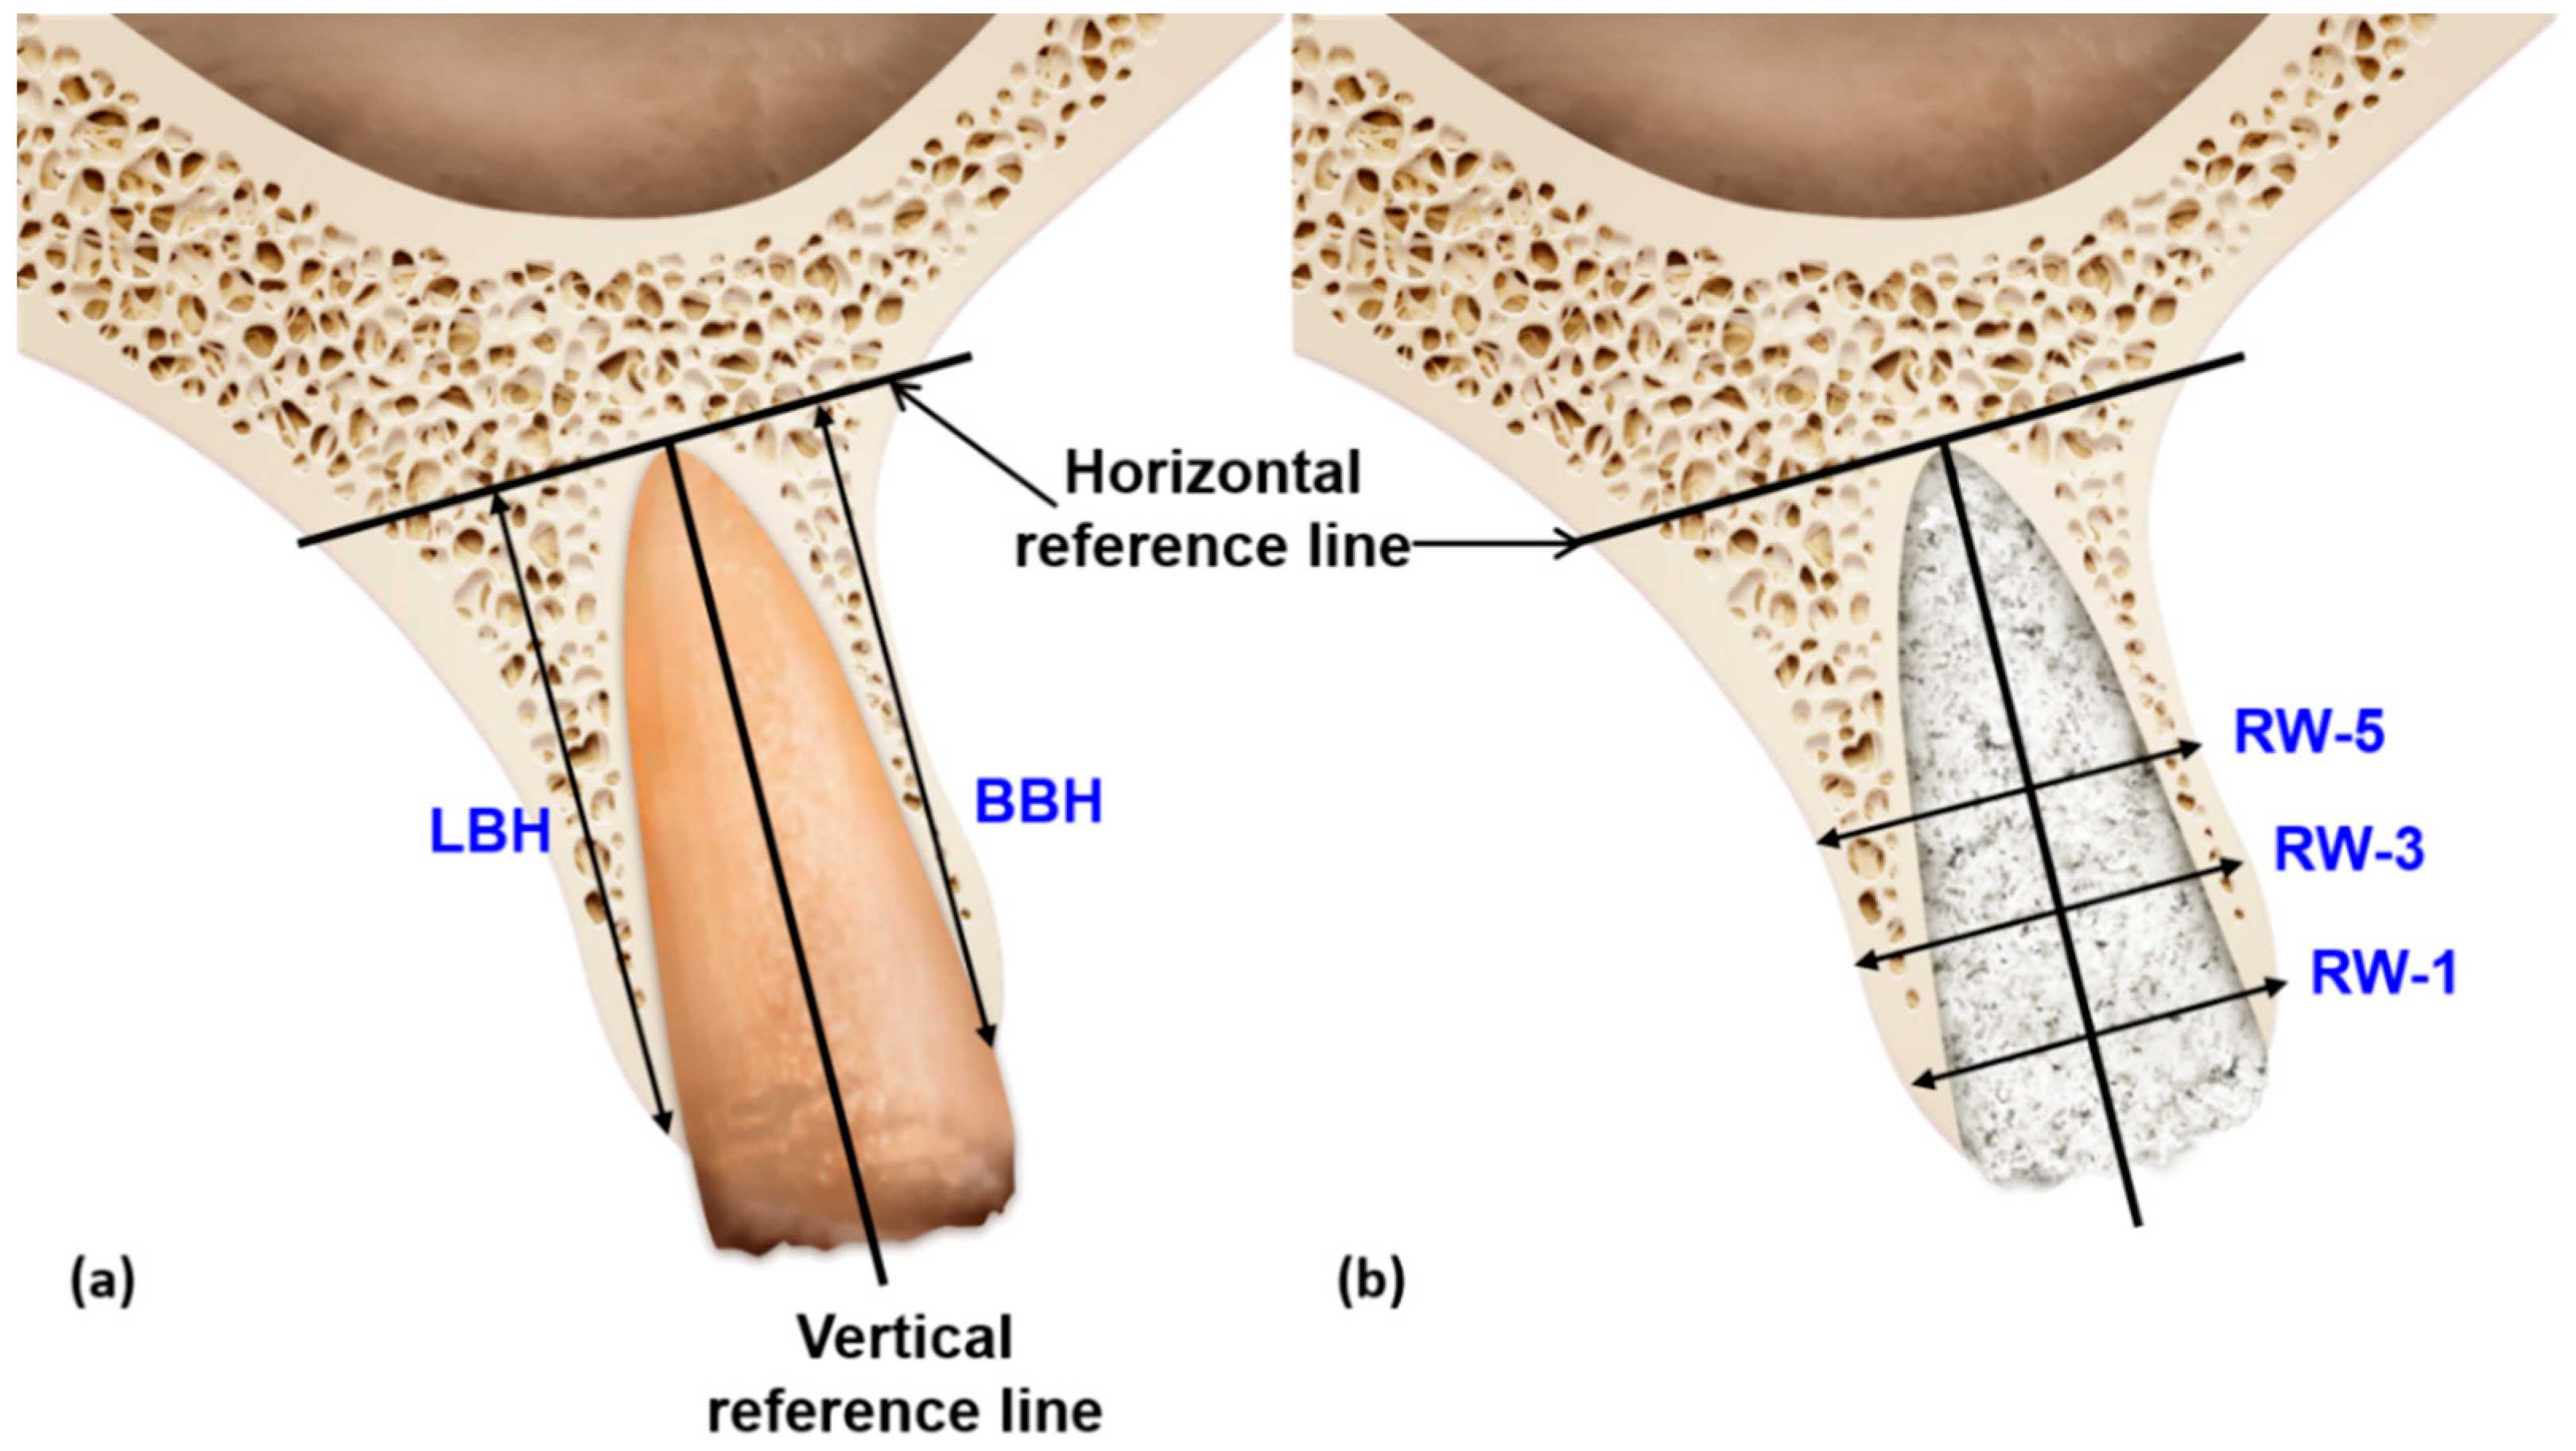

2.6.2. Bone Volume Calculation/Radiographic Assessment

2.7. Radiographic Analysis Using CBCT